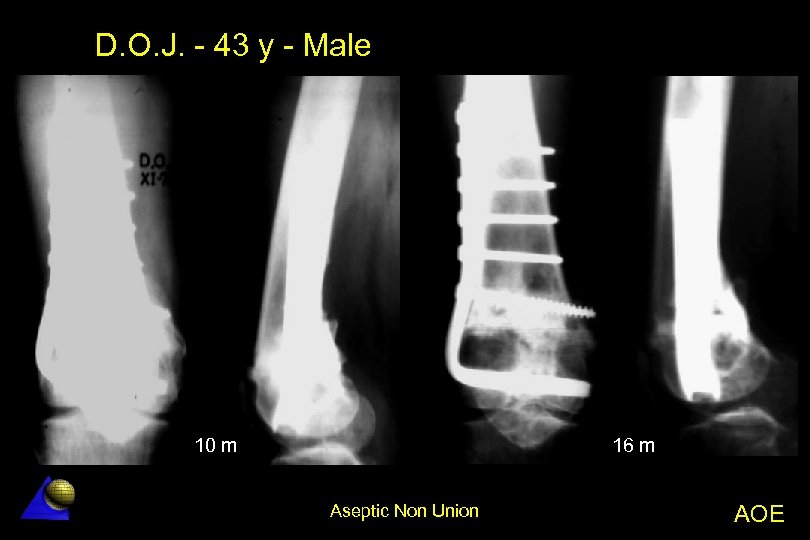

D. O. J. - 43 year old - Male Distal femur non-union - 1. 78 Distal femur metaphyseal non-union l Previous orthopaedic treatment in traction l Angle plate (95º) fixation l Bone healing in 3 months l Aseptic Non Union AOE

D. O. J. - 43 y - Male 10 m 16 m Aseptic Non Union AOE